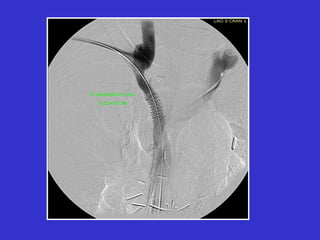

Post-PTA 10 minutes 15 minutes

Elastic Recoil of Central Veins

Immediately

Post-PTA

20 minutes

stent

positioning

Return of original stenosis

due to elastic recoil phenomenon.

Post-PTA Post-Stent

Use of a stent to salvage a failed angioplasty